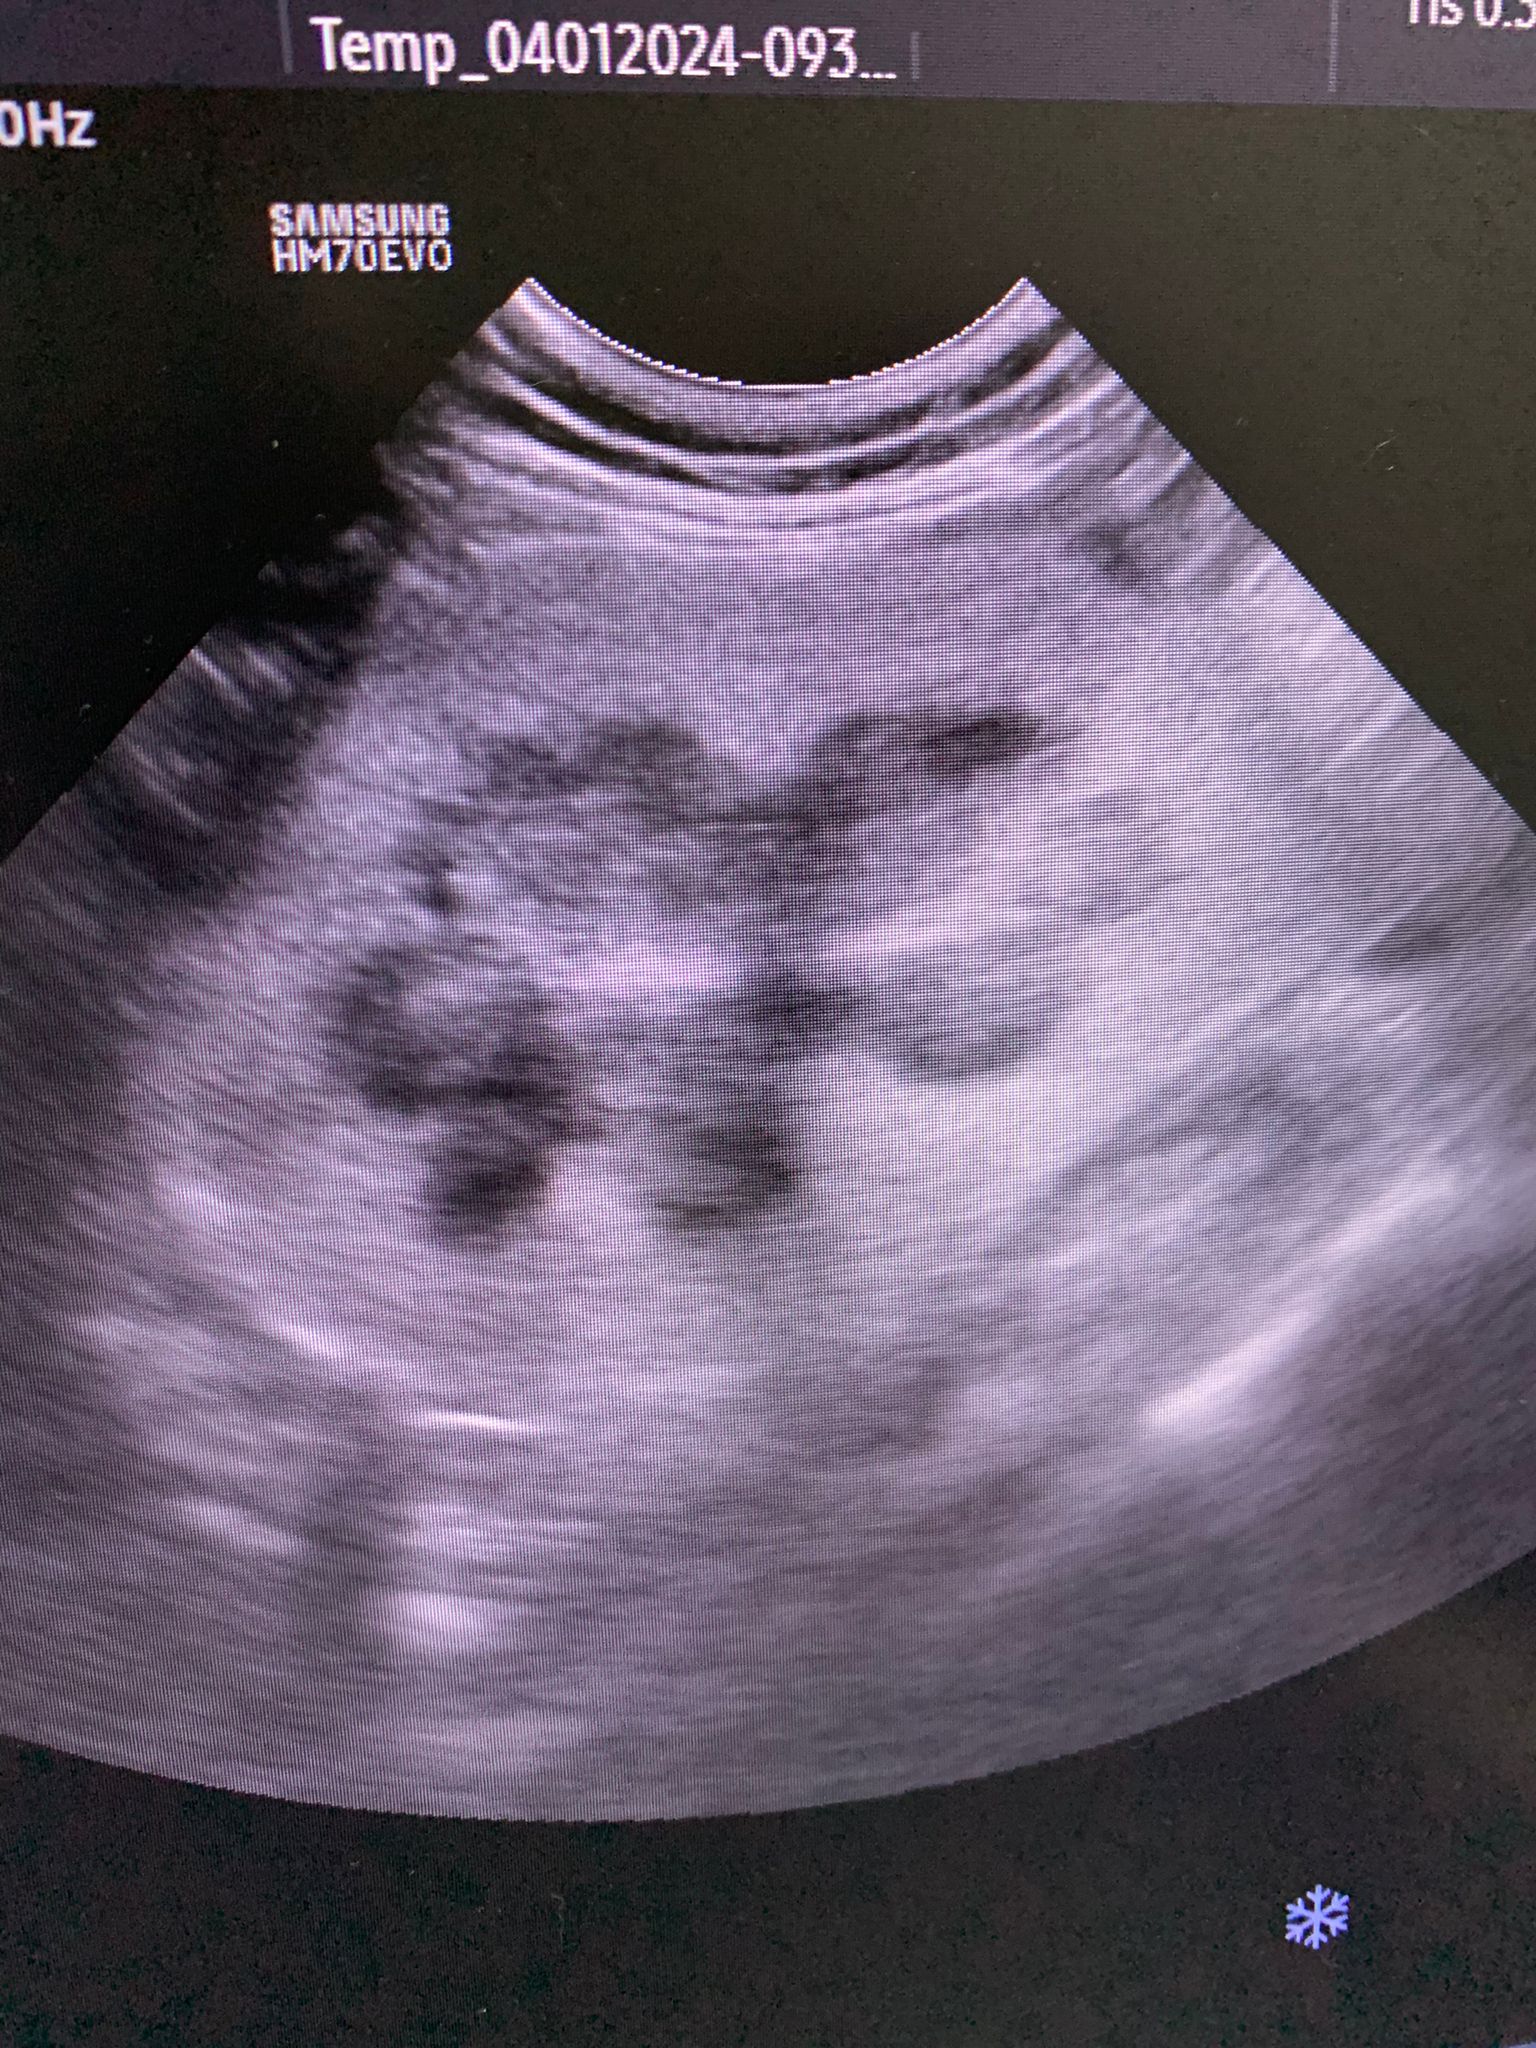

Dr ym scan sweeties, dr flo not involve, both got free fluid ard the kidneys, left kidney is extremely abnormal, right kidney abnormal.

U/s still show the scary fluid ard the kidneys and there is issue w gall bladder also. As the GGT 7 but without confirming is it an obstruction cannot anyhow use. Give le obstruct will rupture.

DDX: Kidney disease (kidney parameters normal but architecture abnormal) FIP, neoplasa, diet (excessive protein, usually concurretn high UREA)